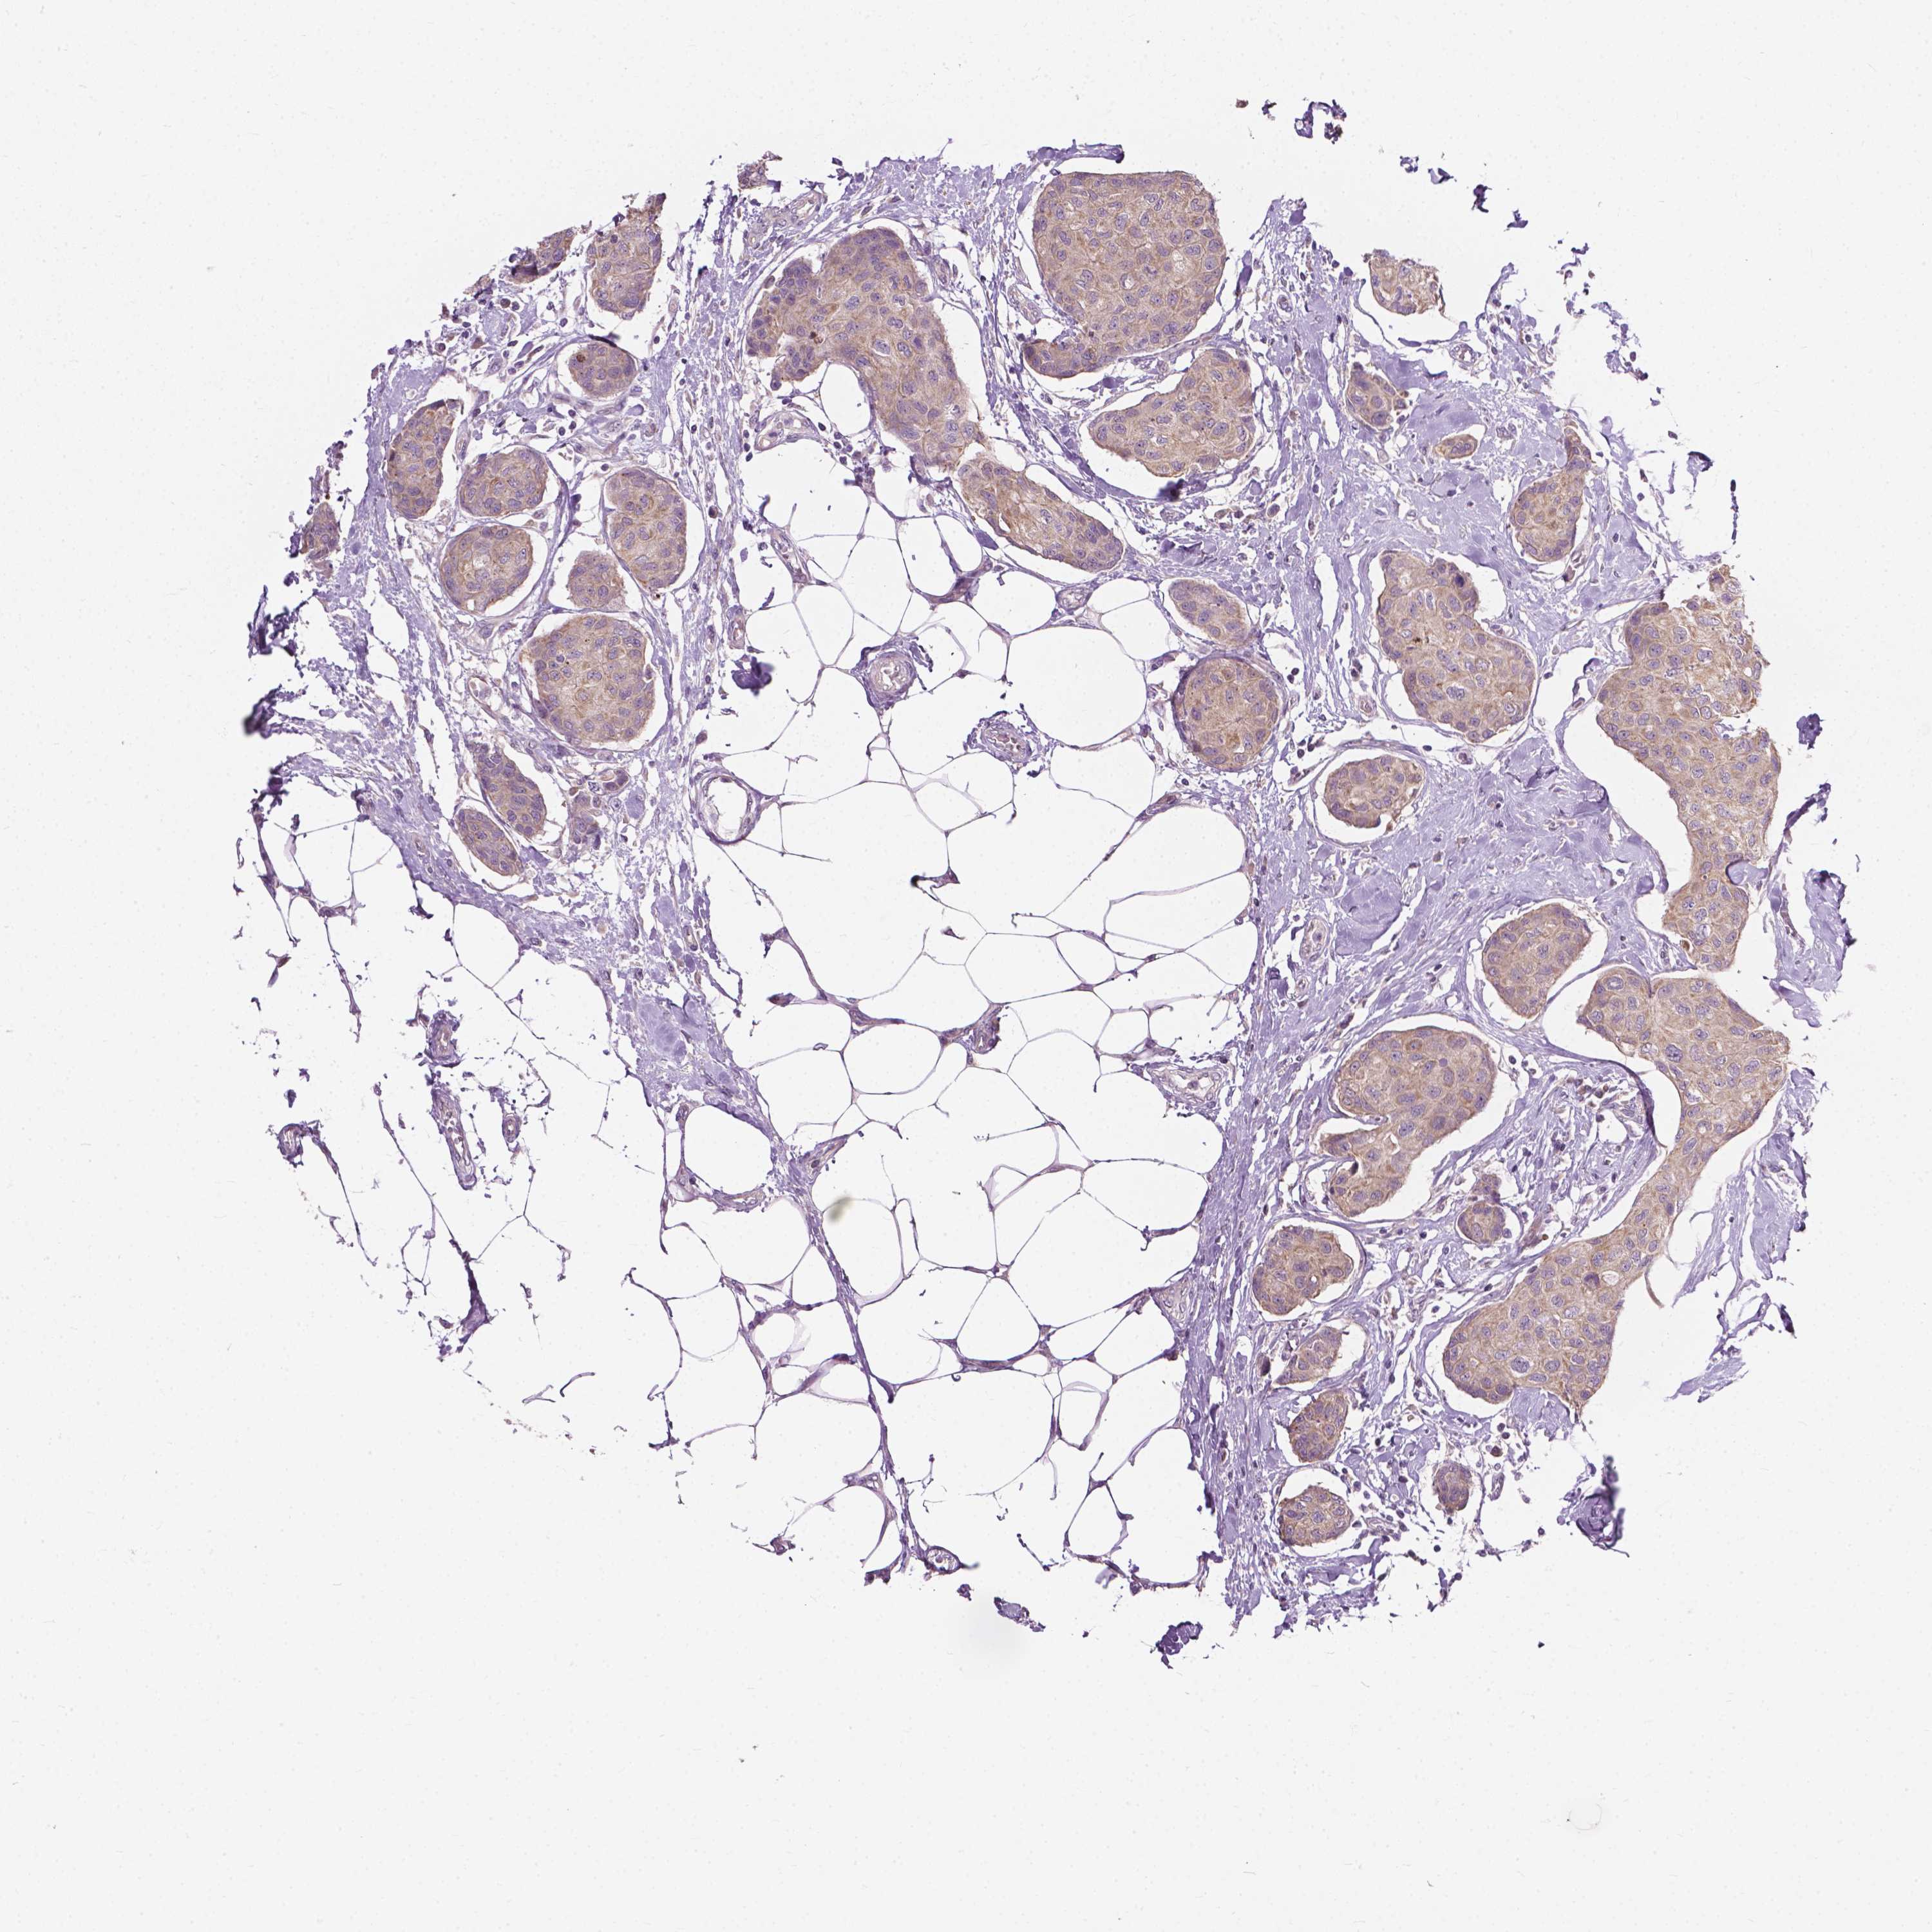

CANCER BREAST CANCER Show tissue menu

BRCA TCGA BRCA VALIDATION PROTEIN EXPRESSION